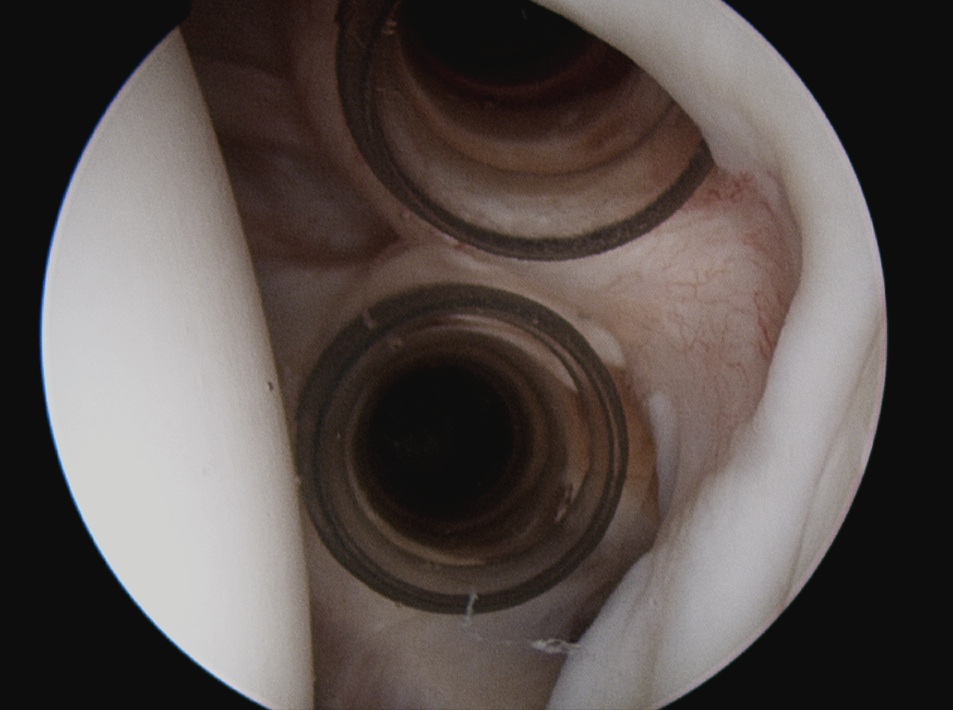

Insert anchors

Inferior anchor at 5.30 o'clock

- curved anchor guide / trans-subscapularis

- on rim of glenoid

Other anchors typically at 3 and 4 o'clock